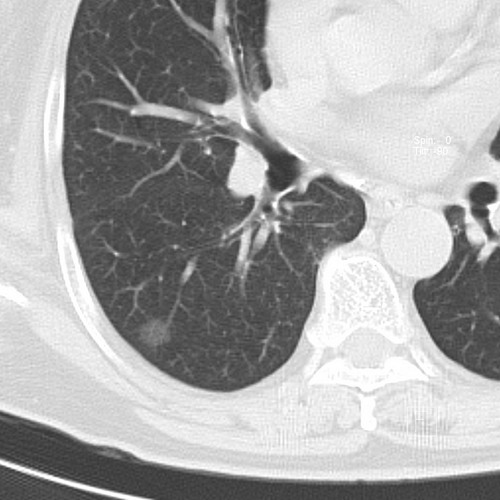

以下是引用sdzyy在2008-11-21 14:57:00的发言:[br]右肺结节影,建议定期复查!支扩,左侧叶间胸膜增厚.

以下是引用卜一在2008-11-21 14:40:00的发言:[br]炎性结节可能!建议定期复查!另:支气管扩张征伴感染!

以下是引用guanaishengming在2008-11-21 17:26:00的发言:[br]右肺结节影,建议定期复查!